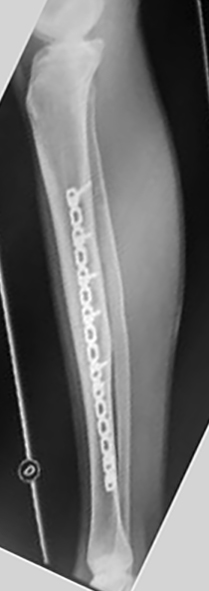

Del total de pacientes, cuatro tuvieron resultados excelentes y cuatro satisfactorios. Todas la fracturas consolidaron en un tiempo medio de 15 semanas (rango: 12-21). Se realizó solo aporte de injerto de esponjosa en un paciente con una pseudoartrosis atrófica tratada previamente con EEF. Todos los pacientes presentaron una movilidad completa de la rodilla y cuello de pie indolora, sin manifestar alteraciones de la marcha y no se encontraron deformidades angulares (mediante examen clínico y radiografías) ni discrepancias en los miembros inferiores significativas con un promedio de hipercrecimiento de 1,6 (rango: -5 a 10) mm. Se autorizó el apoyo parcial a las 5 semanas (rango: 4-8 semanas) y el apoyo total a las 10 (rango: 8 – 13) semanas. Como complicaciones menores, cuatro pacientes presentaron dolor en el implante, sobre todo en aquellos pacientes donde se colocó la placa en el sector interno y en la configuración externa / anterior, sin significado funcional, coordinándose para retirar las mismas (Tabla 1) (Tabla 2) (Figura 1) (Figura 2).

Se utilizaron placas bloqueadas LCP (Synthes, Paoli, PA) en seis pacientes y en dos pacientes placas de reconstrucción bloqueadas (Synthes, Paoli, PA) acorde al largo del hueso (placas largas). En una primera instancia se colocaron fijadores externos en las fracturas expuestas de seis pacientes. Se realizaron limpiezas quirúrgicas en promedio de 2 por paciente (rango: 1-5) y una vez que las partes blandas lo permitieron, se colocó la placa bloqueada. El tiempo promedio para la realización de la cirugía definitiva fue de 8 (rango: 3 - 25) días. En cuatro pacientes se realizó un abordaje antero-interno y se colocó la placa en el sector interno. En dos pacientes se realizó un abordaje externo y se colocó la placa en dicho sector. En otros dos pacientes se realizó un abordaje externo proximal y otro anterior distal, deslizándose la placa desde el sector externo al sector anterior, previo contorneado de la paca. Solo se pudo realizar la técnica MIPO en dos pacientes.